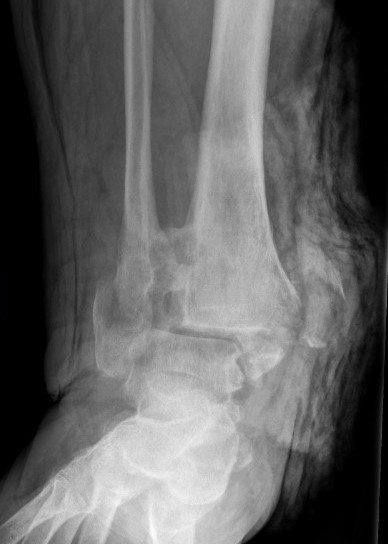

Tibiotalocalcaneal (TTC) / hindfoot nail

Insertion point

- in line with 2nd metatarsal / center of heel pad

- junction of posterior 2/3 and anterior 1/3 heel

- should pass through anterior aspect posterior subtalar joint

- posterior to lateral plantar artery and nerve

Screw fixation

- distal screw fixation in calcaneum +/- talus with jig

- compression

- proximal screws medial to lateral